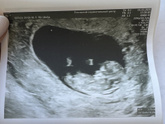

Сходила я все-таки на узи.выделения все также есть.но я же паникерша.врач сказала,что полип мой может кровить.но мне главное ,чтобы отслоек не было.и на узи их нет.Слава Богу??срок 10 недель ровно.выросли на 10.4.токсикоз уже не такой сильный.только … Читать далее